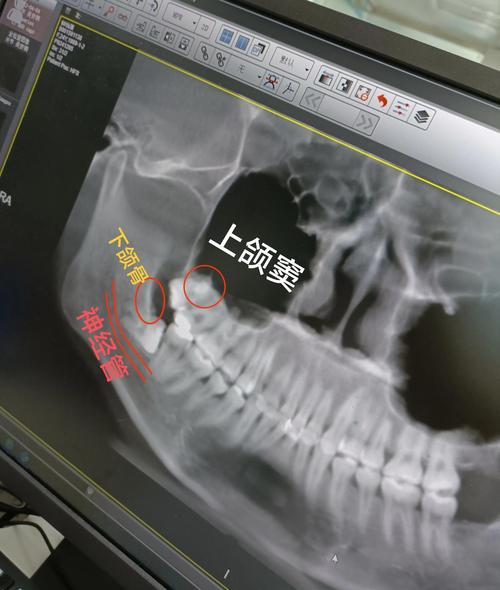

- 影像学检查: 通常会拍摄CBCT(锥形束CT),这是评估上颌窦情况、明确是否有穿孔、穿孔大小、位置、种植体与窦底关系、窦腔内是否有积液或炎症的金标准,普通X光片可能无法清晰显示。